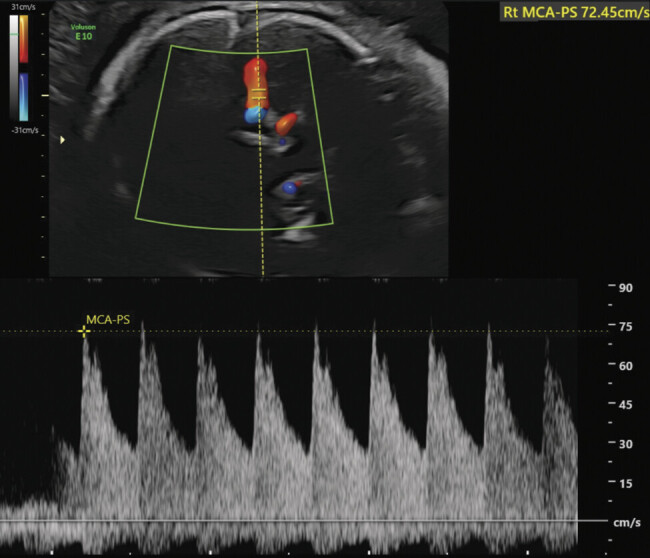

脑室内出血(IVH)是先天性巨细胞病毒(CMV)感染的罕见表现。我们报告一例原发性巨细胞病毒感染与早产以及胎儿贫血、血小板减少症和IVH相关。超声检查发现原因不明的IVH为先天性感染的检查提供了指示。我们的病例表明,在妊娠合并早产时需要详细的超声成像,因为超声诊断的整合可以显著影响管理并改善围产期结局。

Intraventricular hemorrhage (IVH) is an uncommon manifestation of congenital cytomegalovirus (CMV) infection. We report a case of primary CMV infection associated with preterm labor as well as fetal anemia, thrombocytopenia, and IVH. The finding of unexplained IVH on ultrasound provided an indication for testing of congenital infection. Our case indicates the need for detailed sonographic imaging in pregnancies complicated by preterm labor, as the integration of ultrasound diagnosis can significantly impact management and improve perinatal outcomes.